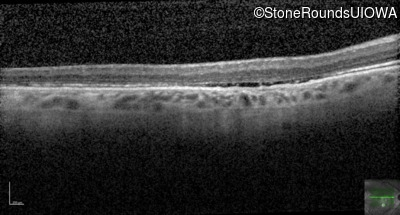

Optical Coherence Tomography - Left - 20/80

Exemplar / OCT Stack

Infrared Fundus Photograph - Right - 20/125 -2